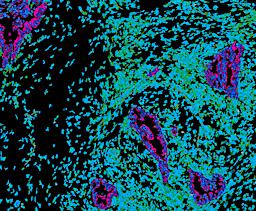

Pancreatic ductal adenocarcinoma is a lethal disease with limited treatment options and poor survival. We studied 83 spatial samples from 31 patients (11 treatment-naïve and 20 treated) using single-cell/nucleus RNA sequencing, bulk-proteogenomics, spatial transcriptomics and cellular imaging. Subpopulations of tumor cells exhibited signatures of proliferation, KRAS signaling, cell stress and epithelial-to-mesenchymal transition. Mapping mutations and copy number events distinguished tumor populations from normal and transitional cells, including acinar-to-ductal metaplasia and pancreatic intraepithelial neoplasia. Pathology-assisted deconvolution of spatial transcriptomic data identified tumor and transitional subpopulations with distinct histological features. We showed coordinated expression of TIGIT in exhausted and regulatory T cells and Nectin in tumor cells. Chemo-resistant samples contain a threefold enrichment of inflammatory cancer-associated fibroblasts that upregulate metallothioneins. Our study reveals a deeper understanding of the intricate substructure of pancreatic ductal adenocarcinoma tumors that could help improve therapy for patients with this disease.